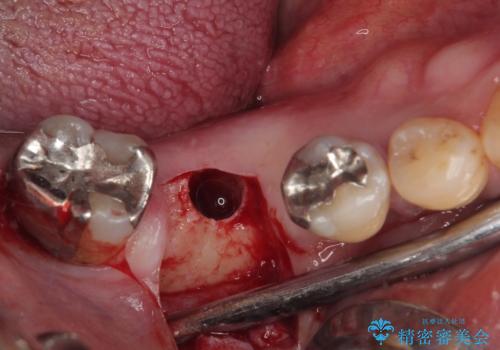

- 奥歯を抜歯してから放置しているとのことで来院された患者様です。

歯が割れて抜歯になってしまったとのことで、咬合力に抵抗できるよう、インプラントによる補綴治療を行うこととしました。

むし歯の放置期間と抜歯してからの放置期間が長く、咬み合わせる上顎の歯がやや伸び出している状態でした。

上顎の部分矯正や対合歯の補綴治療も提案しましたが、今回は欠損部のみの治療を行いました。